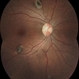

- Optical coherence tomography system

- Optical coherence tomography image over a CHRPE lesion.